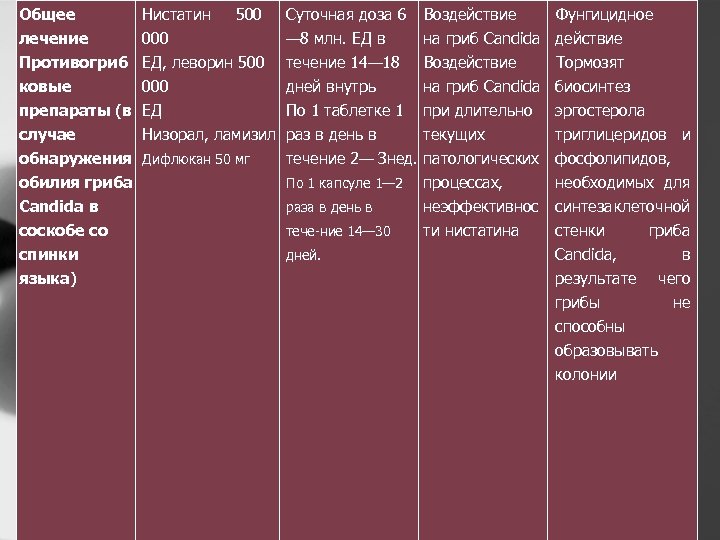

Общее лечение Нистатин 500 000 Суточная доза 6 — 8 млн. ЕД в Воздействие Фунгицидное на гриб Candida действие Противогриб ковые препараты (в случае обнаружения обилия гриба Candida в соскобе со спинки языка) ЕД, леворин 500 000 ЕД Низорал, ламизил течение 14— 18 дней внутрь По 1 таблетке 1 раз в день в течение 2— Знед. Воздействие Тормозят на гриб Candida биосинтез при длительно эргостерола текущих триглицеридов и патологических фосфолипидов, процессах, необходимых для неэффективнос синтеза леточной к ти нистатина стенки гриба Candida, в результате чего грибы не способны образовывать колонии Дифлюкан 50 мг По 1 капсуле 1— 2 раза в день в тече ние 14— 30 дней.